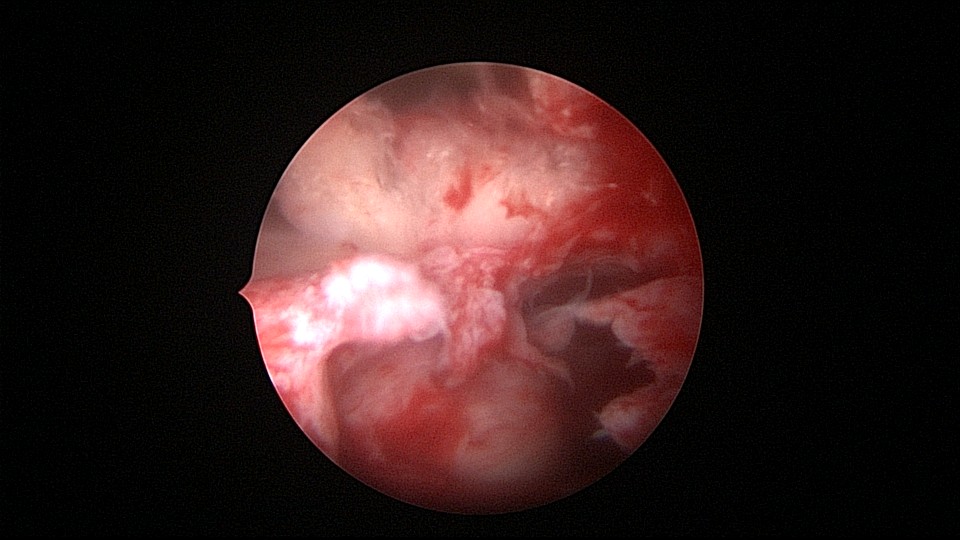

患者55岁,G4P1,顺产1次。安环16年,绝经5年,外院取环失败。子宫前位,宫颈萎缩,宫腔下段左后壁见假道,假道内见肌瘤结节突出,爱母环位置正常,宫腔左侧壁及前壁见占位质脆组织,表面有异常粗大血管。异物钳顺利取出节育环,占位组织病检为内膜样癌。取环造成的假道让病人因祸得福,提前发现了子宫内膜样癌,得以及时手术治疗。